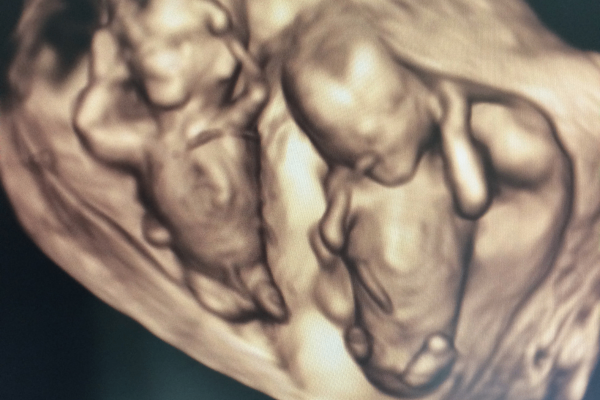

双子を妊娠したとき喜びと同時に、不安になりました。

その後医師に「双子やね。」と言われた時には、「えっ!?」と驚きました。